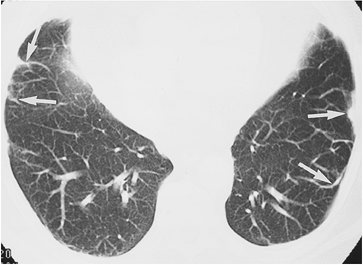

FIGURE 12-1. Usual interstitial pneumonitis. A: Posteroanterior (PA) chest radiograph of a 72-year-old woman with scleroderma shows low lung volumes and bilateral reticular interstitial lung disease. B: CT shows that the reticular opacities have a subpleural, peripheral distribution (arrows).